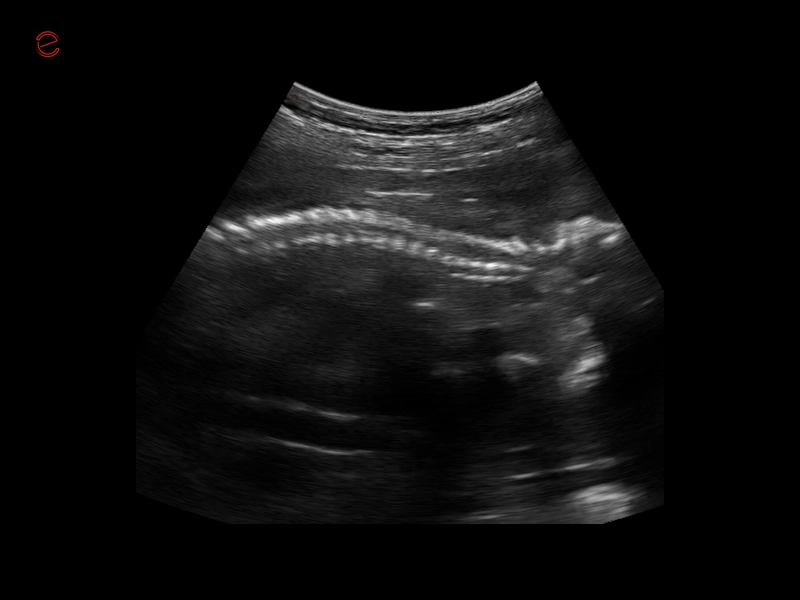

Q7 - WH Spine

Q7 - WH Spine